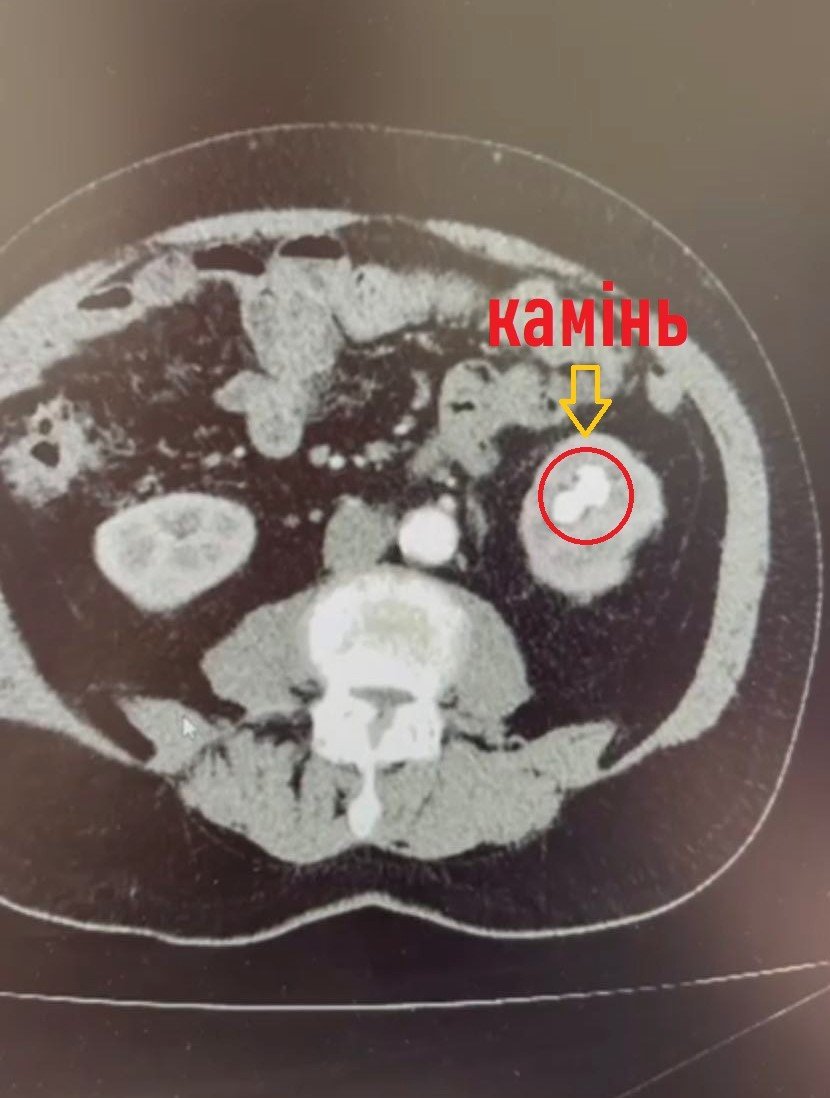

Обстеження на комп’ютерному томографі показали наявність в нирці коралоподібного каменя розміром 38х28 міліметрів та доброякісного пухлинного утвору до 3 сантиметрів у діаметрі з неоднорідним кровотоком у центрі, який знаходився на судинній ніжці лівої нирки.